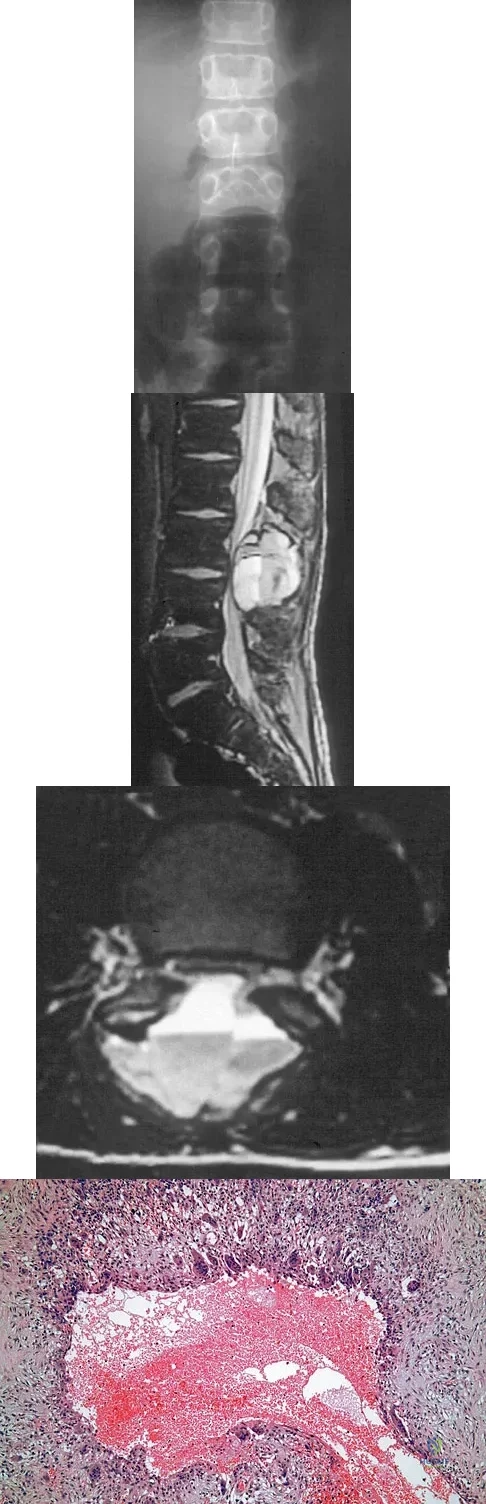

An 8-year-old boy is diagnosed with acute onset cauda equina syndrome. A radiograph, MRI scans, and a biopsy specimen are shown in Figures 57a through 57d. What is the most appropriate treatment?

Explanation